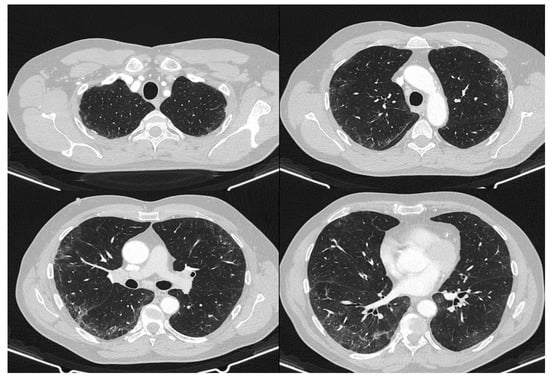

2. Case Report